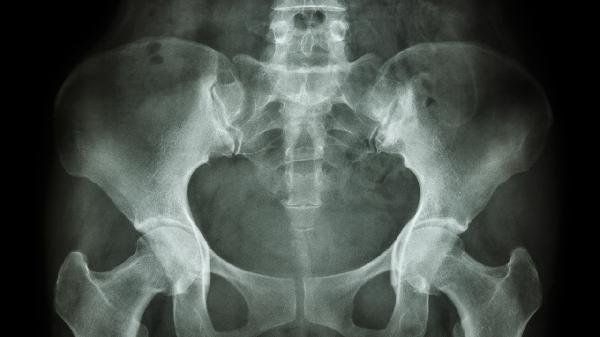

骨盆骨折可出现哪些并发症

骨盆骨折可能引发失血性休克、泌尿系统损伤、神经损伤、深静脉血栓、创伤性关节炎等并发症。骨盆骨折多由高能量外伤导致,需根据损伤程度采取相应治疗。